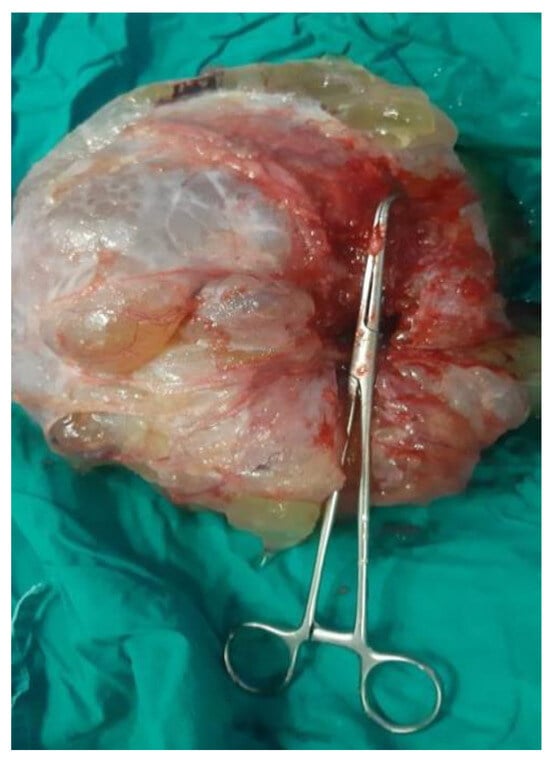

3.2.3. Imaging Findings, Diagnosis, and Differential Diagnosis